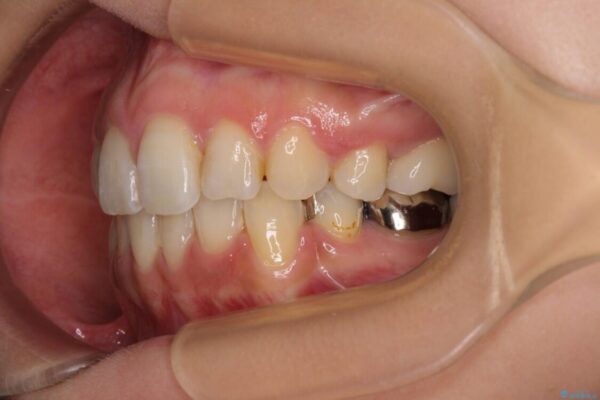

治療後

• デコボコと口元の突出感 ハーフリンガルでの抜歯矯正 治療後画像

治療後について

表側のワイヤー矯正に比べると治療期間は長く、費用も高額となりますが、どうしても目立たせたくないという方にはお勧めの抜歯矯正です。